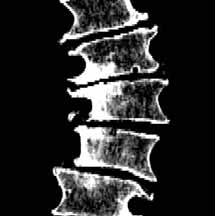

Beispiele für Abklemmungen von Nerven infolge Instabilitäten. Durch den Verlust der Spannkraft der Bandscheiben können sich die Wirbelkörper gegeneinander verschieben und dadurch Nerven einklemmen. Es kann aber auch das Bandscheinegewebe "verrutschen" und dadurch auf Nerven drücken. Dies führt zu Schmerzen im Bein.